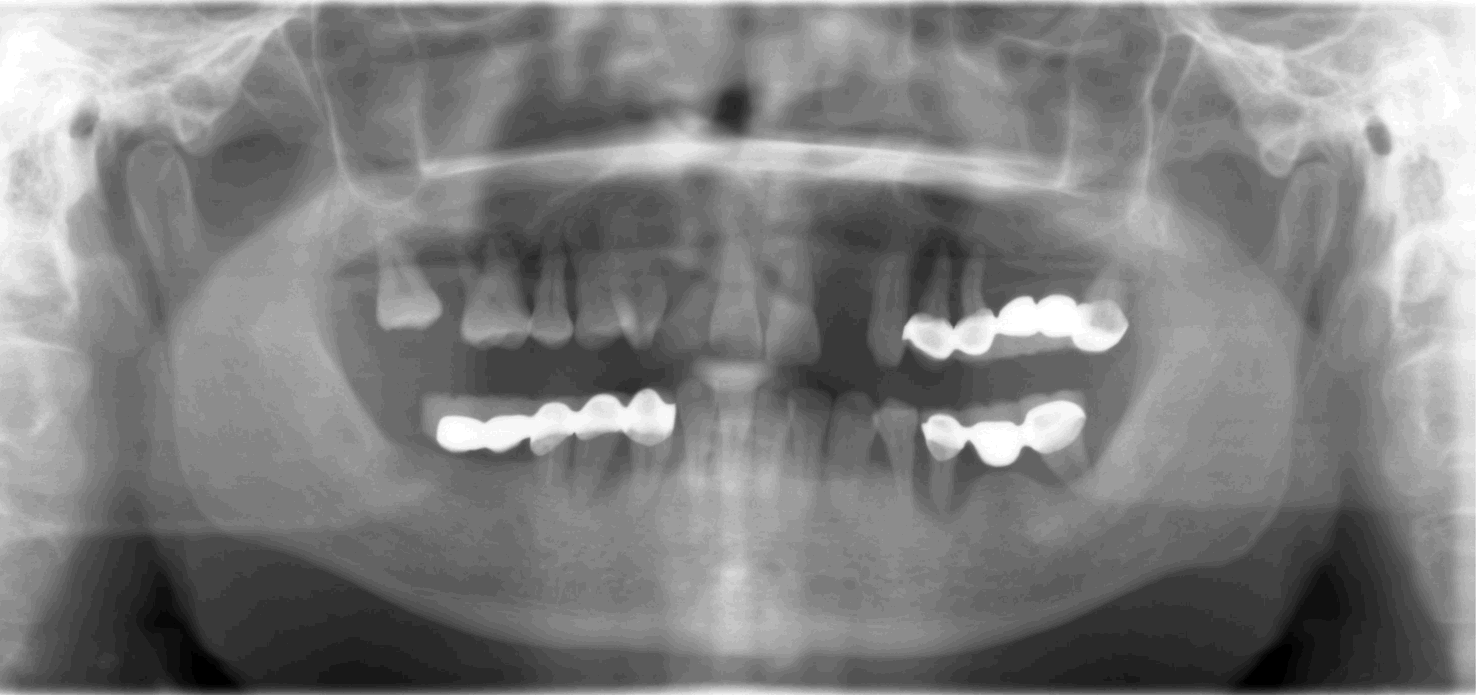

Fig.1 Pre-op panorex showing failing restoration and advanced periodontitis